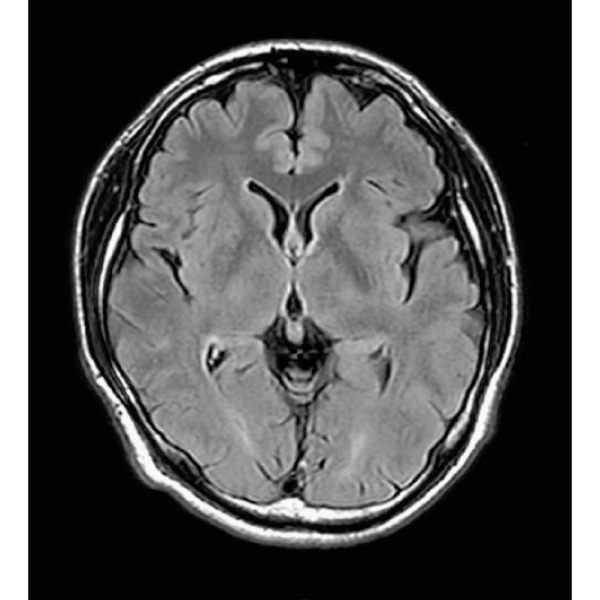

FLAIR, 1:14

FLAIR